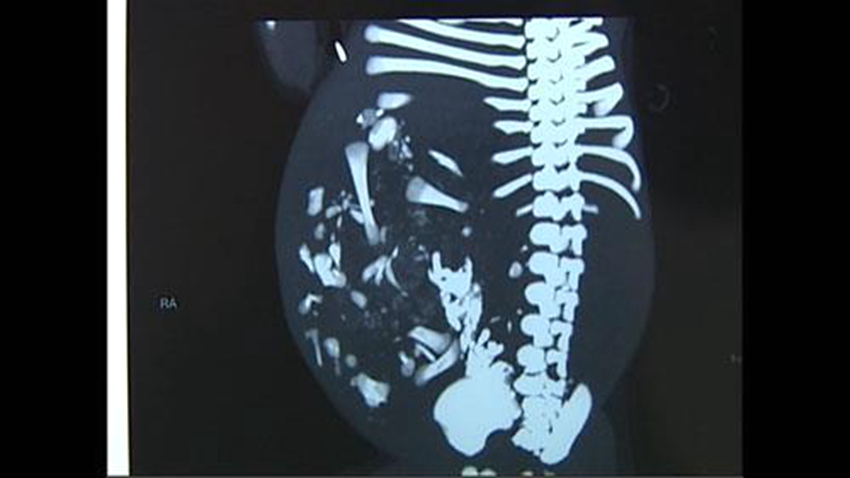

[??? ???? 6? 15?] ??? ? 9? ? ????(苗苗, ?, ??)? ??? ? ?? ‘??’? ??? ??? ???? ??. ???? ??? ?? ?? ?? ??? ?? ??, ?? ??? ?? ???? ??? ?? ? ????.

???(溫州) ?? ?????? ??? ? ??? ?? ????? ??? ??? ????. ?? ?? ?? ???? ??? ??? ?? ??? ??? ?? ?? ‘???(胎中胎)’? ??? ??? ????.

‘?????(parasitic twin)’?? ??? ‘???’? ???? 50? ?? 1? ????, ?? ????? 100 ? ??, ?? ????? 20? ? ????? ??? ??? ????. (??: ???)